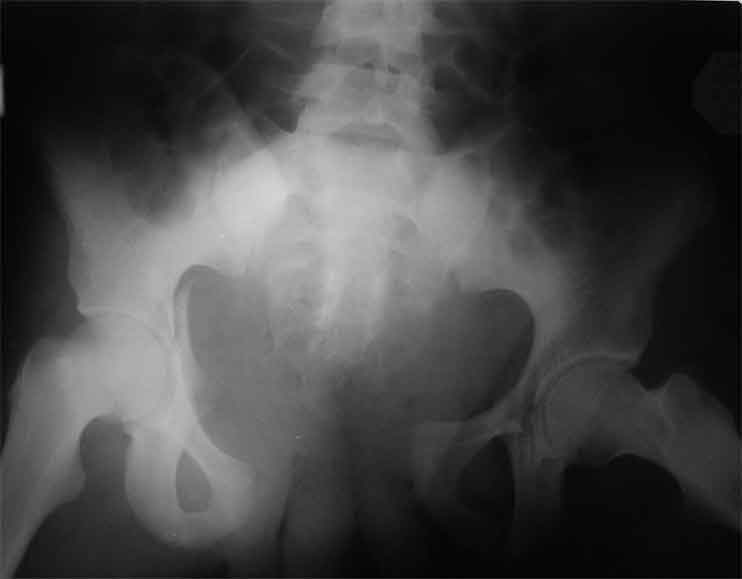

Уважаемые коллеги, сложный случай, интересует ваше мнение. Травма 2 месяца назад, в результате ДТП. При поступлении в лечебное учреждение по м/ж выполнено формирование культи на уровне в/3 левого бедра по (травматический дефект левой н/конечности), в послеоперационном периоде раневая инфекция, остеомиелит - экзартикуляция.

Повреждение таза лечилось консервативно. Интересует ваше мнение по поводу тактики лечения, попытаться свести аппаратом, а потом открытый этап (каким доступом/доступами)? другие варианты? С уважением Максим Агалаков